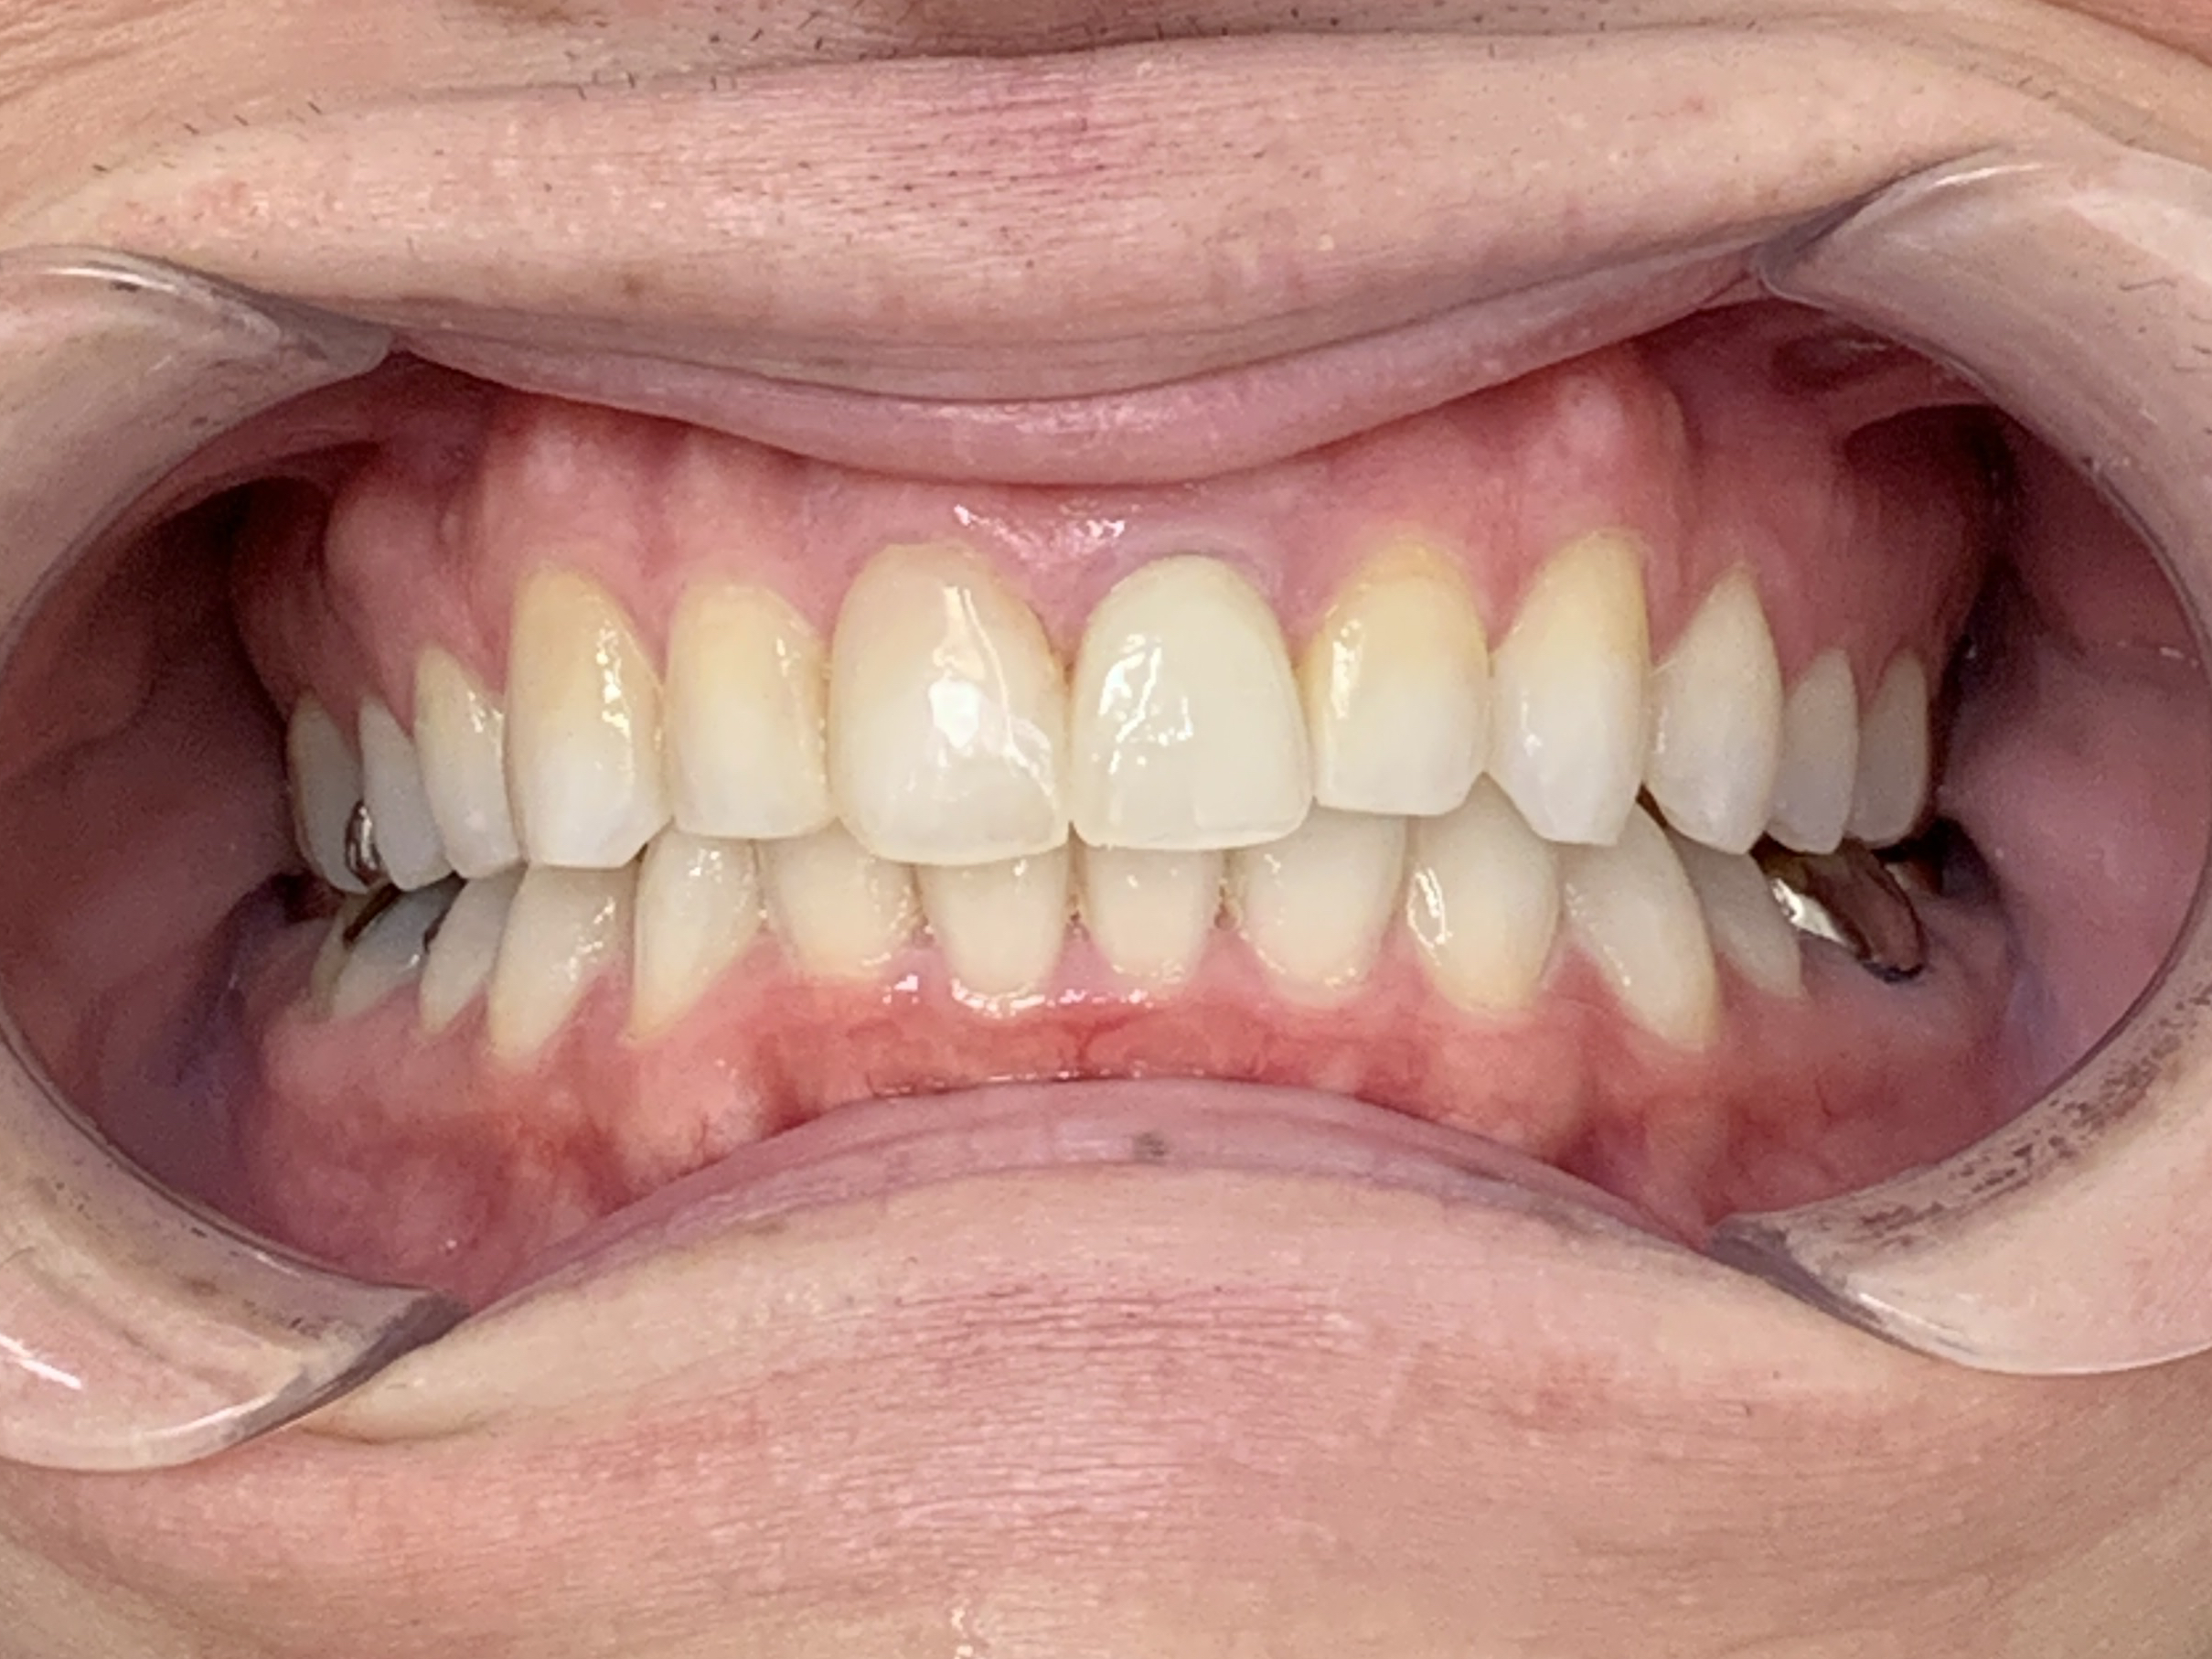

歯がきれいに並び、舌が動かしやすくなり発音もよくなりました。

患者様からは「見た目がよくなっただけでなく、発音も改善できてうれしい」とご満足いただけました。